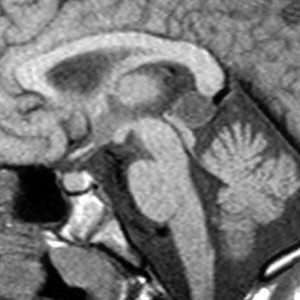

Проявления на МРТ схожи с таковыми на КТ; эпидермоиды часто неотличимы от арахноидальных кист или расширенных ликворных пространств на многих последовательностях.

- T1

- обычно изоинтенсивны ликвору

- часто наблюдается более интенсивный сигнал по сравнению с ликвором по периферии образования

- редко могут иметь гиперинтенсивный сигнал ("белые эпидермоиды")

- обычно изоинтенсивны ликвору (65%)

- слегка гиперинтенсивнее (35%)

- редко гипоинтенсивные, как правило , в случаях так называемых "белых эпидермоидов"

- обычно неоднородный / "грязный" сигнал; выше, чем от ликвора

- остерегайтесь потоковых артефактов от пульсации ликвора, которые могут имитировать подобные изменения

При МРТ головного мозга картина неспецифическая и зависит от содержимого кисты. Если она не содержит жира, то имеет ликворную интенсивность сигнала . В таком случае эпидермоидная киста трудно отличима от арахноидальной, хотя, как правило, не столь однородная. На МРТ типа FLAIR и диффузионно-взвешенных МРТ изображениях содержимое эпидермоидов светлее ликворного. Жировое содержимое, такие эпидермоиды еще называют холестеатомой, приводит к высокому сигналу на Т1-взвешенных МРТ головного мозга. Видимо, он обусловлен липидами, но не холестеролом. На Т2-взвешенных МРТ головного мозга он менее интенсивен чем ликвор. Контуры эпидермоидов всегда четкие. Холестеатомы составляют всего 3-5% от эпидермоидов. В 15-20% случаев встречается кальцификация по переферии кисты. Редко наблюдается контрастирование стенок.